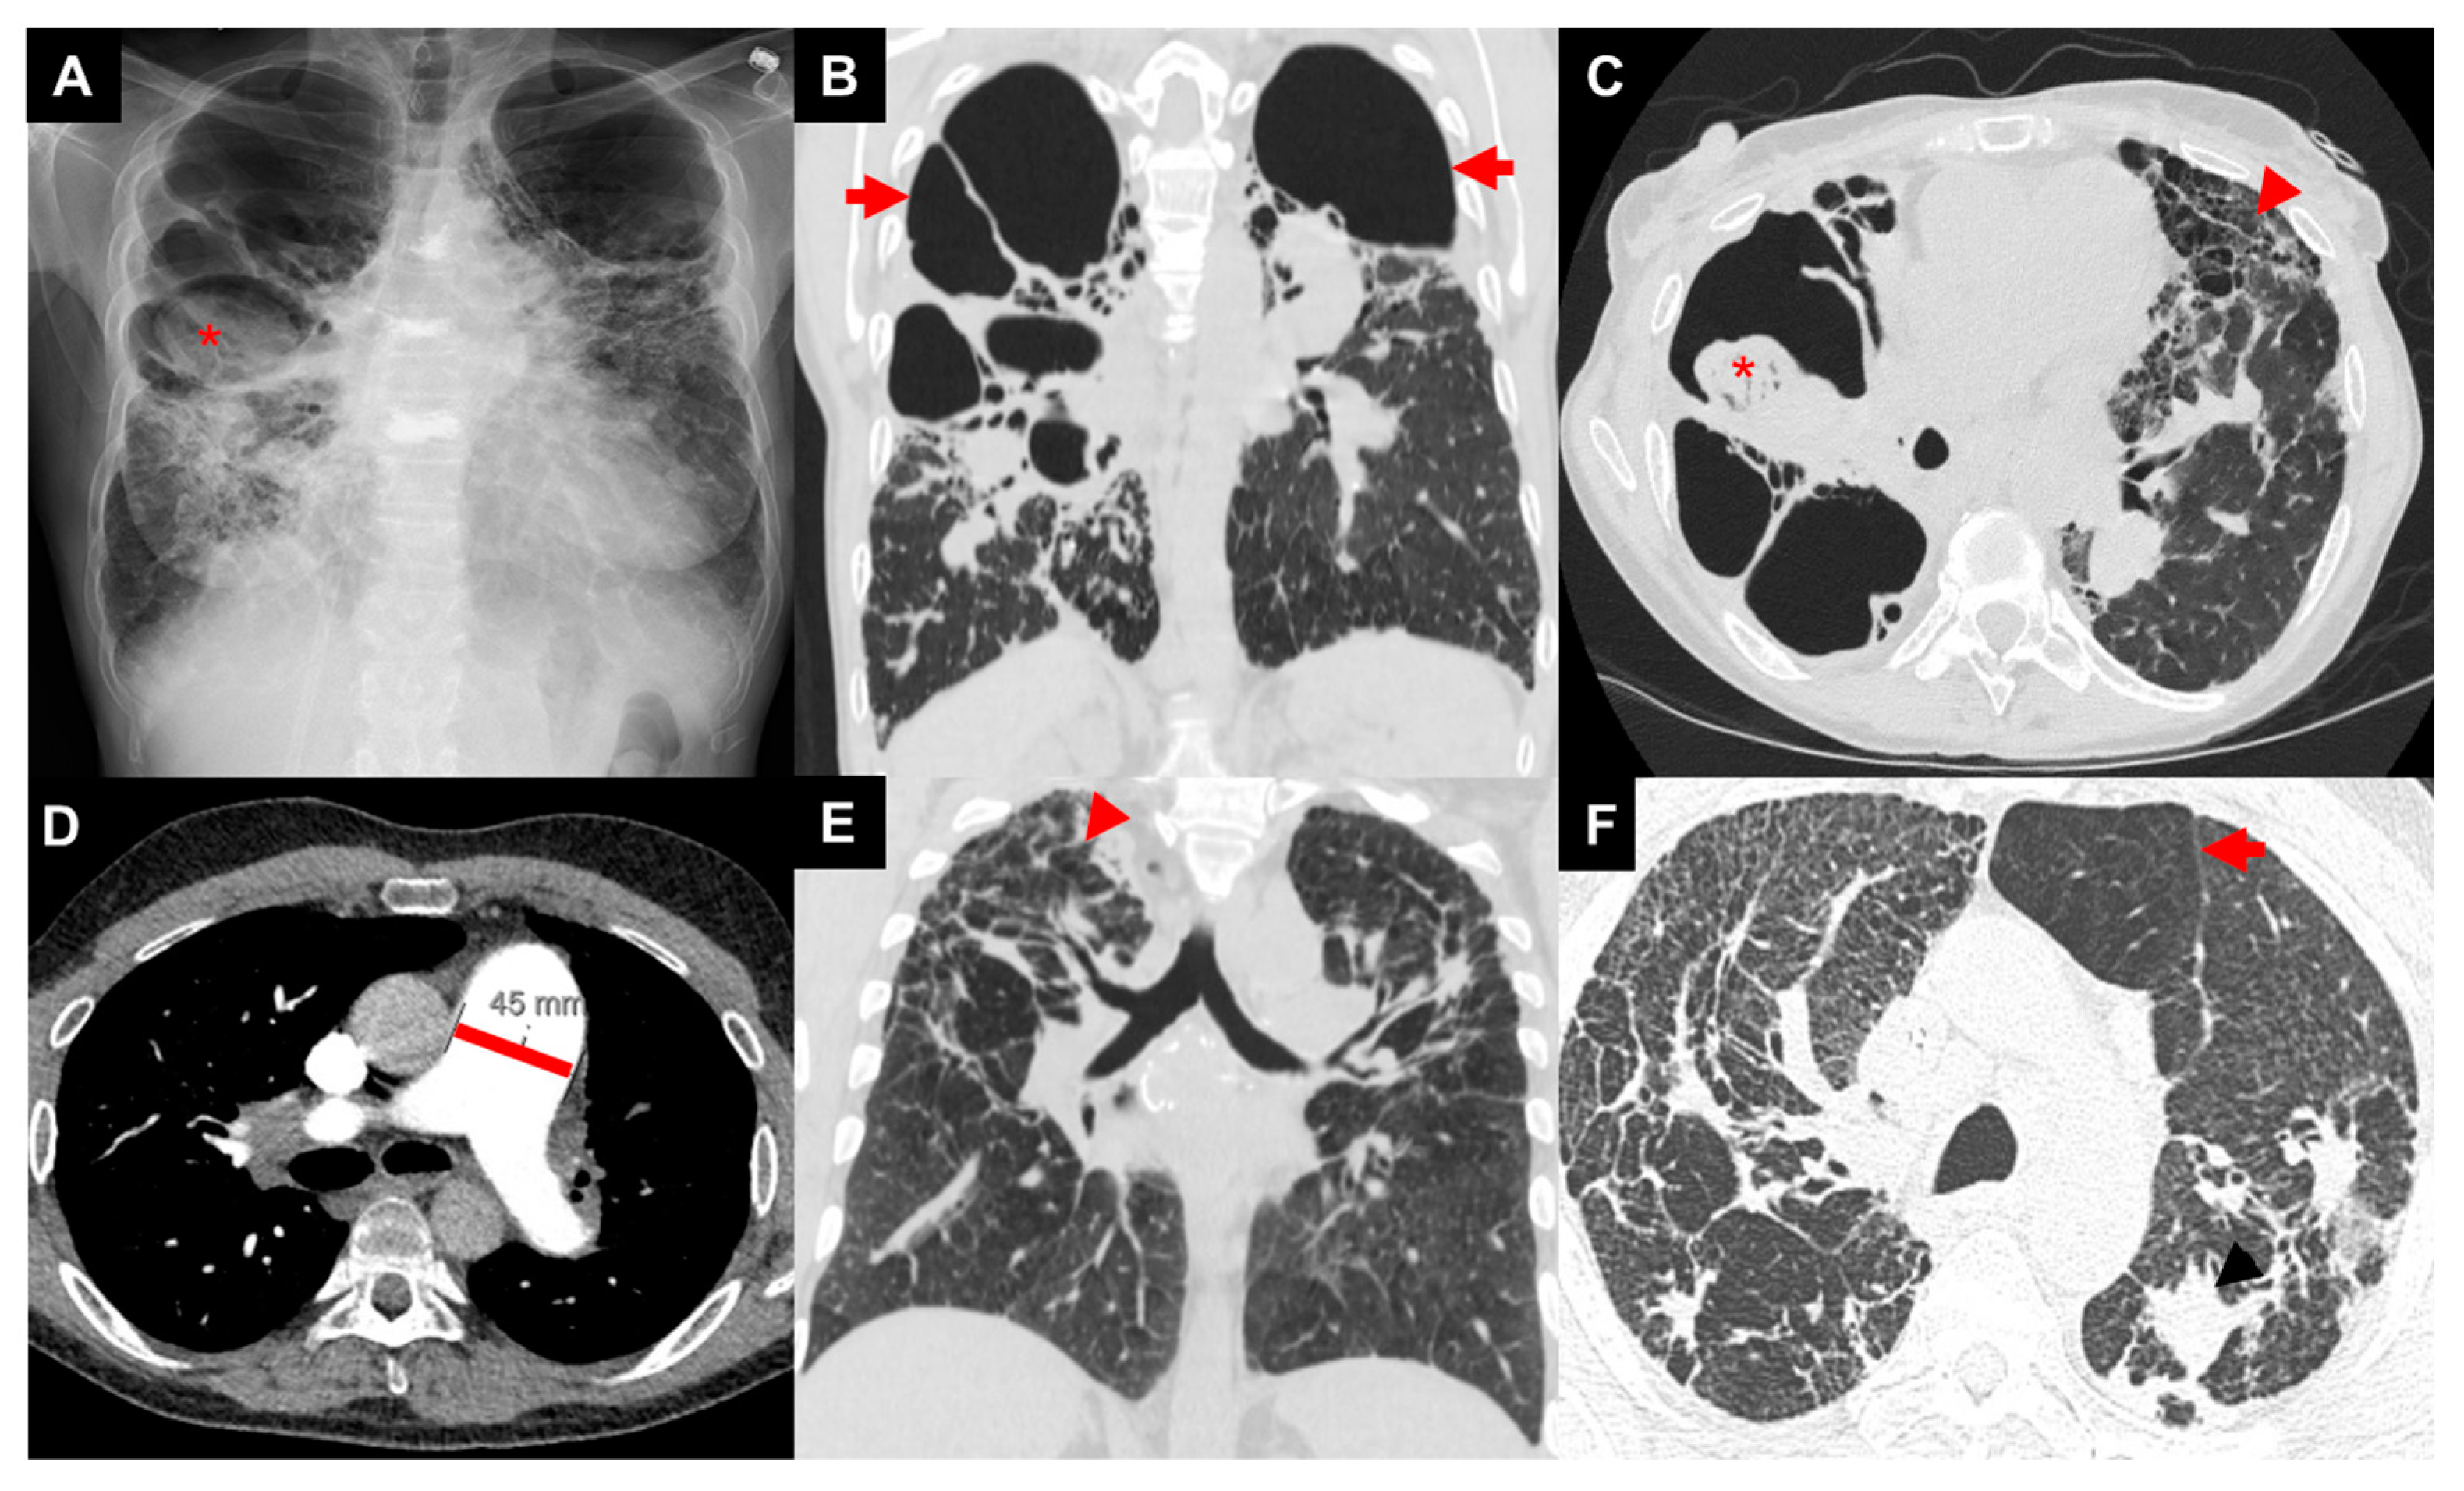

On chest radiography (CXR), Scadding stage 4 is defined by the presence of pulmonary fibrosis, as mentioned above (Figure 2) [7]. Patients may have upper-lobe-predominant linear opacities projecting from the hilum with dilated airways [54]. High-resolution computed tomography (HRCT) gives a more comprehensive understanding of anatomic changes. Three major patterns of fibrotic sarcoidosis can be identified: central bronchial distortion, peripheral upper zone honeycombing, and diffuse hilar linear opacities (Figure 2) [11,55,56]. Fibrocystic opacities may track along the airways from the hilum to peribronchovascular and fissural regions [11]. HRCT may show subpleural honeycombing, fibrocystic lesions larger than traditional honeycombing, paracicatricial emphysema, and development of mycetomas [11,57]. Granulomatous infiltration of the airways will cause airway distortion, airway angulation, and diffuse wall thickening [7,56]. HRCT can also help screen for sarcoidosis-associated pulmonary hypertension by using a ratio of main pulmonary artery diameter/ascending aorta diameter (MPAD/AAD) greater than 1, evaluating for a dilated pulmonary artery greater than 30 mm (Figure 2), and using a ratio of the diameter of the main pulmonary artery/body surface area (MPA/BSA) greater than 16 [3,11,58].

Figure 2.

Images of three patients with advanced pulmonary sarcoidosis: patient 1 with biapical cavities and mycetoma (asterisk) on chest X-ray (A), large biapical bronchiectatic cavities (arrows) on coronal image of CT chest (B), right apical mycetoma (asterisk) and extensive left-sided upper-zone predominant fibrosis (arrow head) of anterior lung on axial image of CT chest (C); patient 2 with enlarged pulmonary artery diameter (45 mm) on axial image of CT chest (D); patient 3 with bilateral irregular reticular and nodular fibrosis (arrow head) on coronal image of CT chest (E) with air trapping (arrow) on axial image of CT chest (F).